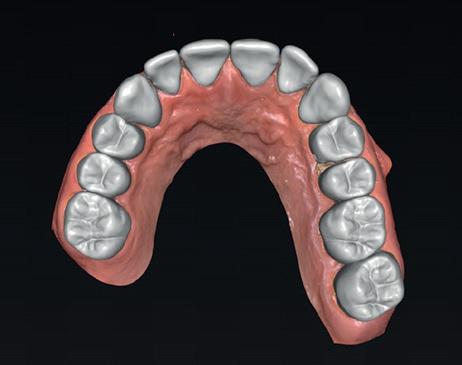

• Intra-orale scan voor studiemodellen, proefopstelling en beoordelen ruimte palatinaal

Na 4 weken intra-orale scan voor de etsbrug en kleurbepaling bij de technicus

• Plaatsen van de etsbrug met een composietcement

Voordat er gescand kon worden voor een etsbrug, werd een studiemodel vervaardigd om met de technicus te overleggen of er voldoende ruimte was voor 2 centrale incisieven in de mesio-distale zin en of er voldoende ruimte was in occlusie voor de vleugels van de etsbrug. Er hoeft enkel nog aan de 12 en 22 pala-

tinaal geslepen te worden als er geen 1,5 mm ruimte voor de vleugels behaald kan worden. De ruimte was op de dunste plekken 1 mm, dus een kleine preparatie in de 12 en 22 palatinaal was nodig. Omdat de kaak volledig afgevlakt was en dun was geworden, kunnen de dummies van de etsbrug enkel op de kaak “gelegd worden”, maar daarbij zijn er geen papillen en staat de cervicale rand van de dummies net voor de kaak. Een esthetisch resultaat kan daarmee niet behaald worden. Daarom is een aanvulling van de zachte weefsels in de breedte nodig, als het creëren van een emergence profile, waarbij het oogst alsof de gebitselementen uit het weefsel vertrekken.